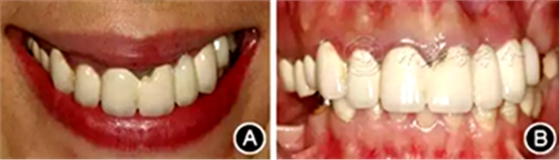

口腔衛(wèi)生狀況一般,菌斑指數(shù)0~2,鄰面少量軟垢;牙齦齦緣鮮紅、水腫、質(zhì)軟,出血指數(shù)2~3,余牙牙齦輕度水腫,出血指數(shù)0~2;全口探診深度2~3 mm,個別位點探診深度達4~5 mm,鄰面可探及附著喪失;未查及牙齒松動及根分叉病變;烤瓷固定橋修復(fù),冠邊緣密合度欠佳,位于齦下1~2 mm;、唇側(cè)崩瓷,邊緣暴露;上前牙牙齦線不協(xié)調(diào);缺失,右下后牙可摘局部義齒修復(fù),固定橋修復(fù);近中面銀汞充填,近中懸突及繼發(fā)齲;上前牙覆蓋下前牙牙冠的1/2~2/3(圖1)。

圖1 患者初診時臨床照片 A:正面微笑像;B:正面口內(nèi)像